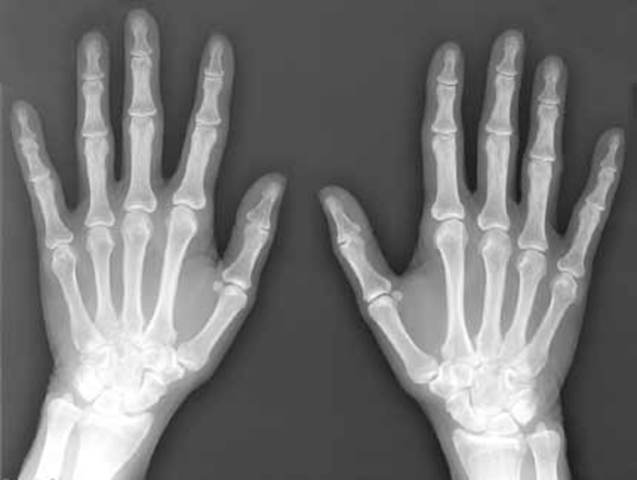

• Discovery of X-Rays

Discovery of X-Rays

In the time of American Imperialism, one of the biggest discoveries in history occured. Wilhelm Conrad Roentgen discovers X-rays.